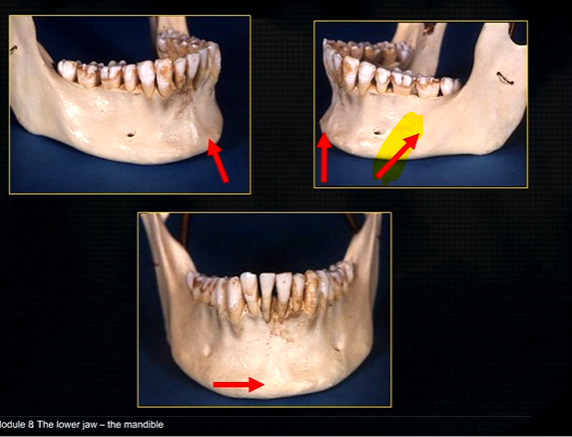

periapical region

can see honeycombed pattern

mental foramen - black radiolucency - near 1st and 2nd premolars

sockets of the teeth are represented by thin, white, opaque lines → ‘ lamina dura’

dense, white, radiopaque line → dense bone of mylohyoid ridge

underneath mylohyoid ridge - looks more radiolucent → this is due to the lingual indentation of submandibular fossa

dense cortical bone of the lower border

radiolucent shadow created by the lingual pit

lower occlusal

small bony spurs of the genial tubercles